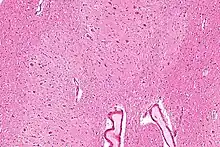

Sección sagital por el hemisferio derecho cerebelar. La oliva derecha, "el núcleo olivar inferior" se ha cortado en el plano sagital — de frente hacia atrás. (Núcleo dentado, "nucleus dentatus" marcado arriba.